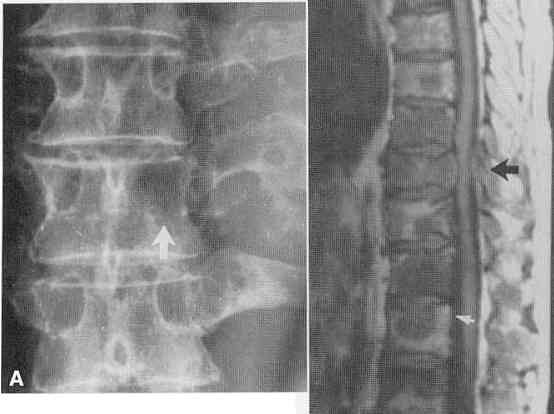

• MRI is also more sensitive than plain Xrays. A woman had severe pain in her arm , the Xray was read as normal but the MRI was markedly abnormal (see here) she later developed a pathologic fracture see here. (other cases:  see spine , spine, here and MRI) see MRI showing a pathologic fracture from lymphoma here. The specific MRI rechnique will influence the way bone mets appear (go here)

• Some bone cancers make the bone look " too white" called osteoblastic mets of the pelvis or osteoblastic spine , CT of blastic mets here and here and here